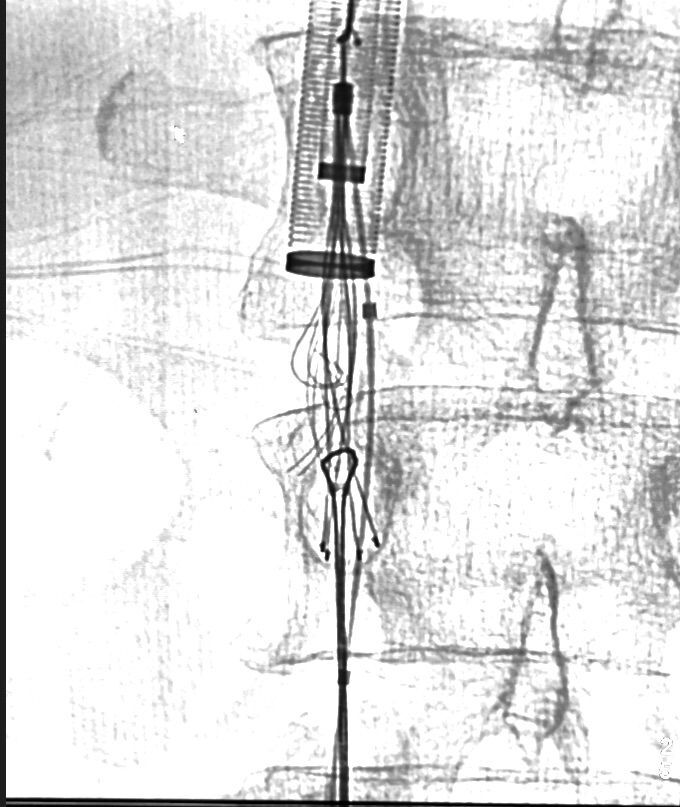

Vena cava filters are used to treat deep vein thrombosis and pulmonary embolism. Despite the extensive literature on these filters, there is still no reliable evidence that they improve clinical results or mortality in patients with deep vein thrombosis. There are also increasing reports of complications from indiscriminate use, with a complication rate of approximately 19%. Complications include penetration into the vein wall, involvement of adjacent organs, fracture, embolization of filter fragments, and deep vein thrombosis. We describe the successful removal of a vena cava filter 4 years after implantation for inferior vena cava thrombosis. The procedure was performed using common endovascular surgery devices.